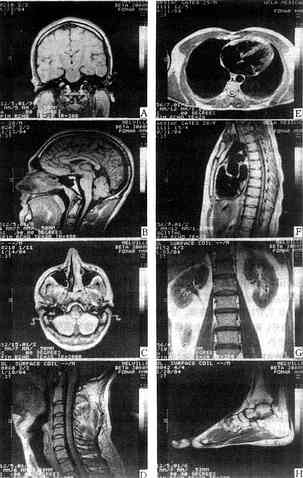

图1-5-4 不同器官结构的MRI

A.B.C.颅脑的冠状面、矢状面及横断面的MRI D.颈部的矢状面MRI

E.F.心脏大血管的横断面和矢状面MRI G.躯干冠状面MRI H.足的矢状面MRI

心血管的血液由于流动迅速,使发射MR信号的氢原子核离开接收范围之外,所以测不到MR信号,在T1WI或T2WI中均呈黑影,这就是流空效应(flowing Void)。这一效应使心腔和血管显影(图1-5-4),是CT所不能比拟的。

MRI可获得人体横面、冠状面、矢状面及任何方向断面的图像,有利于病变的三维定位。一般CT则难于作到直接三维显示,需采用重建的方法才能获得状面或矢状面图像以及三维重建立体像(图1-5-4)。